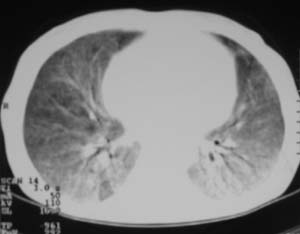

以下是引用zjzjr在2007-9-20 12:29:00的发言:[br]双肺磨玻璃改变,考虑肺水肿.

以下是引用yangzongshan在2007-9-20 18:29:00的发言:[br]两肺毛玻璃样改变,其内可见肺纹理影,无胸腔积液,故考虑肺泡蛋白沉积症

以下是引用276894491在2007-9-20 13:40:00的发言:[br]考虑肺水肿;外源性过敏性肺炎不排除。

以下是引用逸风在2007-9-20 20:45:00的发言:[br]两肺磨玻璃样改变,临床病史短,发热,考虑病毒感染合并右肺代偿性肺气肿.待排肺水肿,病史短,不支持肺泡蛋白沉着症.